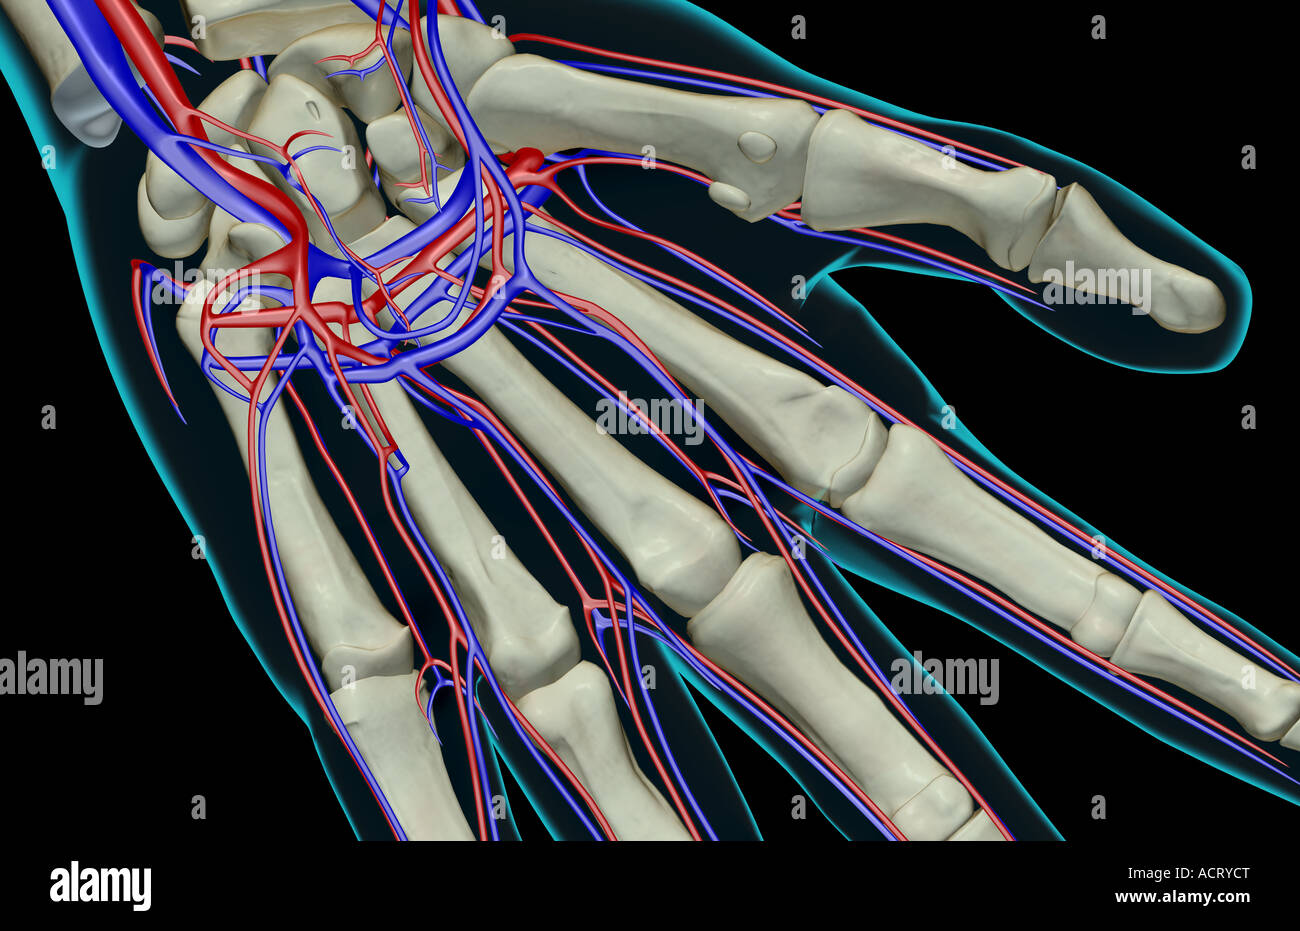

The blood supply of the hand Stock Photohttps://www.alamy.com/image-license-details/?v=1https://www.alamy.com/stock-photo-the-blood-supply-of-the-hand-13221191.html

The blood supply of the hand Stock Photohttps://www.alamy.com/image-license-details/?v=1https://www.alamy.com/stock-photo-the-blood-supply-of-the-hand-13221191.htmlRFACRYCT–The blood supply of the hand